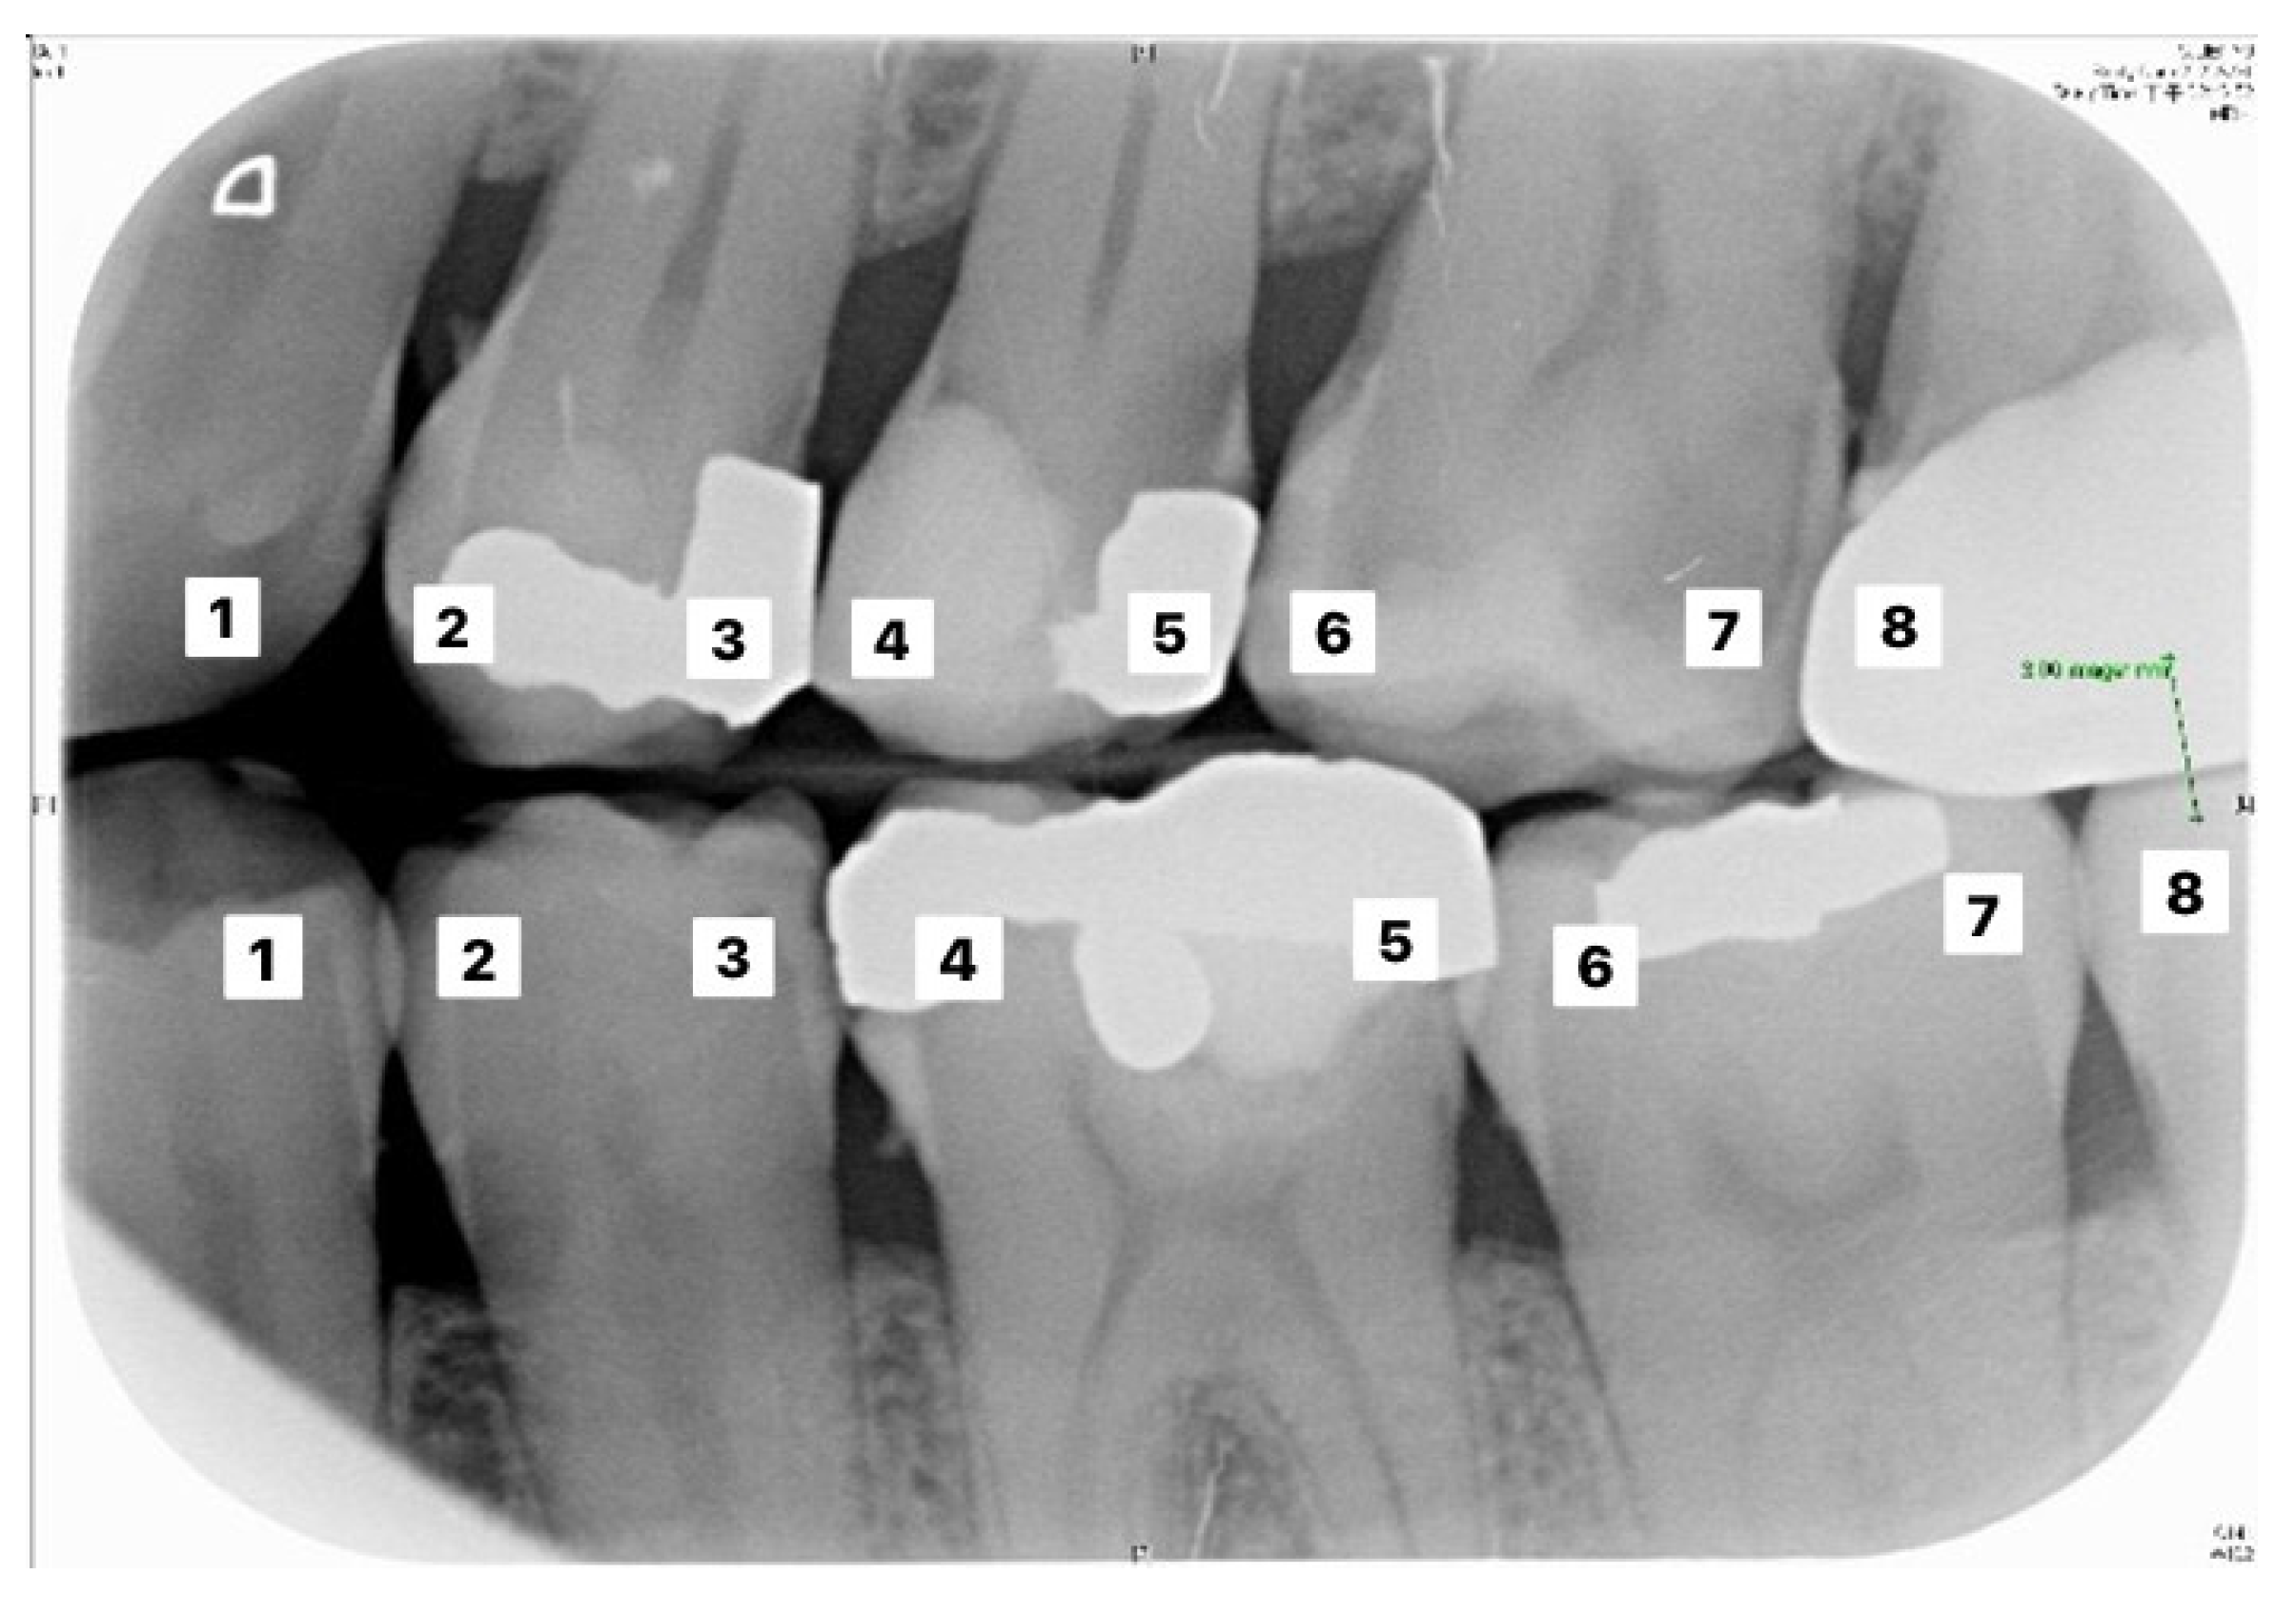

Table 6 and Table 7 correspond to the judgment of the upper and lower rows of teeth in Figure 10. Results show that the accuracy of the proposed model for judging the restorations was 95.56%, which is an improvement compared to Lin et al. [30], with an accuracy of 90.23%. The proposed method in Lin et al. [30] first enhanced the classification features of the image, and then added the regular term and impulse, before establishing a CNN model with the ReLU function. With regard to judging caries, the proposed model in this study showed an accuracy of 90.30%, which was also an improvement compared to Singh and Sehgal [31], with an accuracy of 80.00%, which used a neural network classifier to classify caries. Table 8 and Table 9 are the truth tables of different CNN models.

Figure 10.

Image example of outer teeth for validation (from left to right, in order of 1–8).